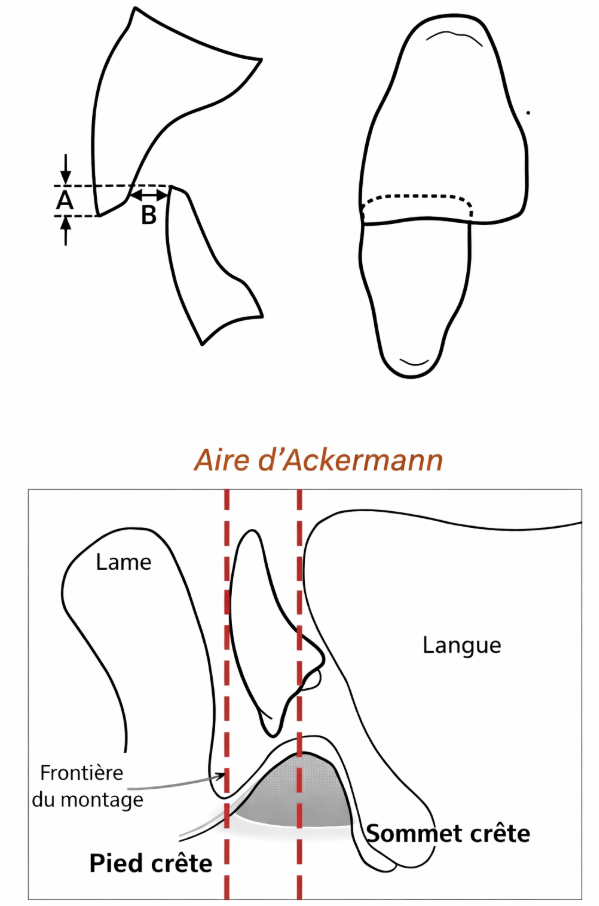

- Les dents antéro-inférieures devront être montées dans l’aire de sustentation d’Ackermann (l’espace délimité par le sommet de la crête antérieure et de son versant vestibulaire).

Plan horizontal :

Sa position s’inscrit dans l’aire de sustentation d’Ackermann. Elle est montée sur le versant externe de la crête (talon de la dent placé de 1 à 2 mm en avant de la crête).

Sa position s’inscrit dans l’aire de sustentation.

Plan horizontal :

Sa position s’inscrit dans l’aire de sustentation dans le prolongement de l’incisive latérale.